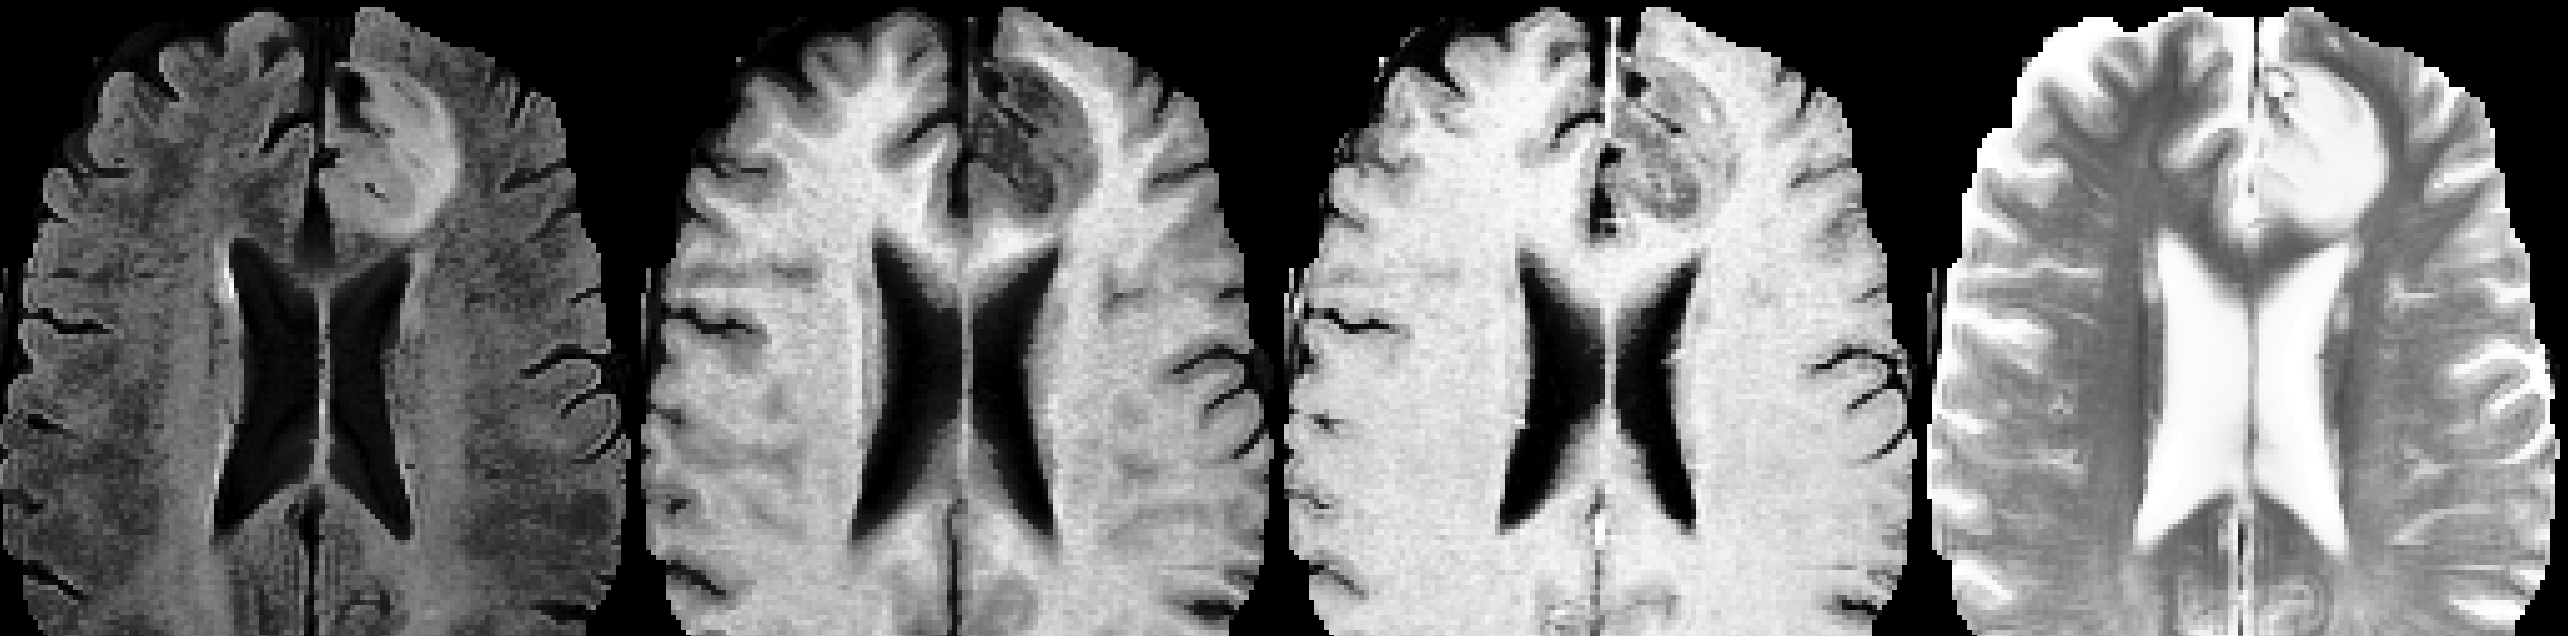

All experiments, including classification and segmentation tasks using CNNs and LLMs, were conducted with the same cleaned data to ensure a fair comparison. The BraTS 2020 dataset consists of 365 patients, each with four MRI scans (T1, T1ce, T2, and FLAIR) providing 95 axial slices per scan, resulting in 95x128x128 voxel arrays of intensity. The scans were processed as integer arrays (0-256 per pixel), normalized, and centered around the glioma using radiologist-annotated segmentations. All images were resized to a consistent shape of (4, 95, 128, 128). To focus on the capabilities of the CNN and LLM models, no additional image processing techniques, such as filtering or histogram equalization, were applied. The dataset was split into separate cohorts: 310 training, 62 validation (for each of 5-folds), and 55 test samples (15%). Care was taken to ensure that all scans and slices for a single patient were kept within the same cohort, preventing any overlap of information between the training, validation, and test sets. The dataset was also imbalanced in that there are far fewer LGG patients compared to the HGG patients. All training and validation data was balanced by oversampling the LGG class. Sample patient scans from the BraTS 2020 dataset are given in Figure 1 and Figure 2.

Refer to caption

Figure 1: Scan modality visualization for an LGG patient Bakas et al. [2019, 2017], Menze et al. [2015], Bakas et al. , noa .

Figure 2: Scan modality visualization for an HGG patient Bakas et al. [2019, 2017], Menze et al. [2015], Bakas et al. , noa .